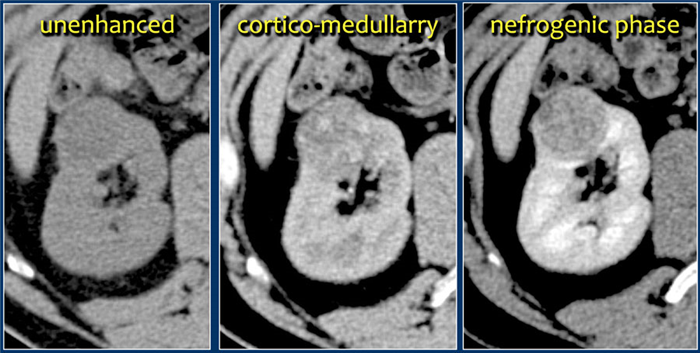

• Острый инфаркт:

о Сегментарный или субсегментарный инфаркт:

- Четко отграниченный, дорсальные или вентральные сегментарные (или субсегментарные) области пониженного накопления контраста

- Демаркационная граница между нормальной, накапливающей контраст паренхимой, и измененной неконтрастируемой паренхимой

- Основание клина направлено в сторону почечной капсулы, верхушка - в сторону ворот почки

о Признак кортикального ободка:

- Сохранение капсулярного/субкапсулярного накопления контраста

- Встречают в 50% случаев инфаркта почки (интактный околопочечный коллатеральный кровоток)

- Обычно встречают спустя 6-8 ч после инфаркта